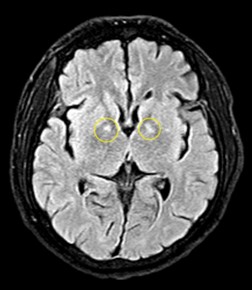

Bác sĩ điều trị, TS. Nguyễn Đăng Đức – Trung tâm Chống độc cho biết: Ba trường hợp trên đều đốt than củi để sưởi ấm trong phòng kín dẫn đến ngộ độc khí CO. Hiện các bệnh nhân đang được điều trị hồi sức tích cực, theo dõi, đánh giá các tổn thương và nguy cơ di chứng. Hiện bệnh nhân nam có tổn thương não. Các bệnh nhân nữ tổn thương tim, suy tim, tiêu cơ tim và nguy cơ di chứng với tâm thần, thần kinh rất cao.

Hình ảnh tổn thương não của bệnh nhân nam